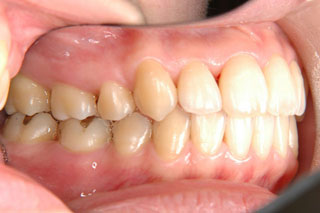

2年半ほどの治療で、装置を撤去し保定治療に移行しています。概ね緊密な臼歯の咬合と前歯の被蓋が確立されました。

保定治療を開始してから2年半が経過していますが、良好な咬合の安定が維持されています。見た目だけではなく、中心位マウントの咬合器にて顎位のズレを計測していますが、計測値は1mm未満の数値である事を確認しています。理想的には中心位=咬合位かも知れませんが、多少の遊びは必ず出てきます。しかしながら最初からルーズなゴールを目指していたら、的を外してしまうでしょう。できれば、ピンポイントで理想を目指したいものです。